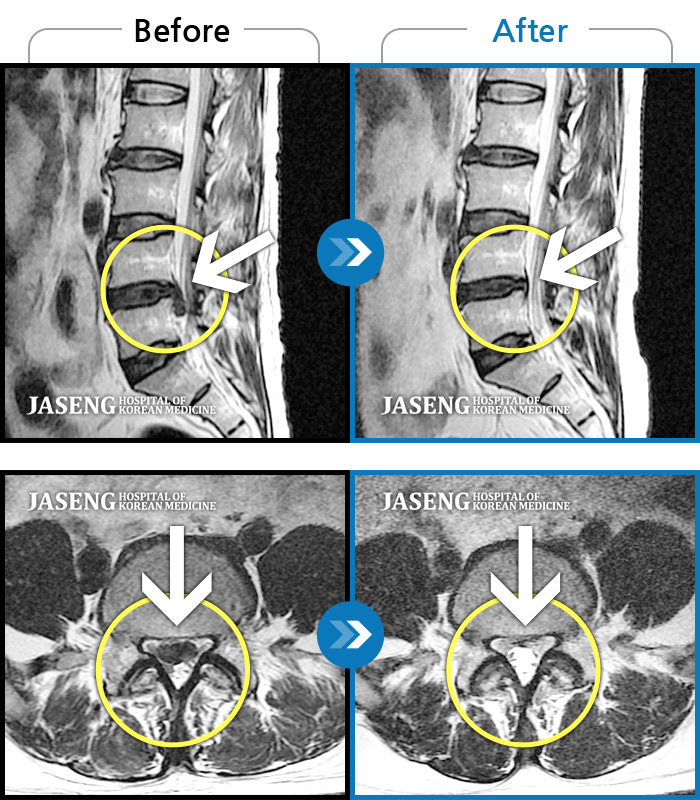

허리디스크

일산 · 김태용 원장

허리와 우측다리가 심하게 저렸다.

촬영시기

2020.05.07 ~ 2020.12.29

2021.02.26